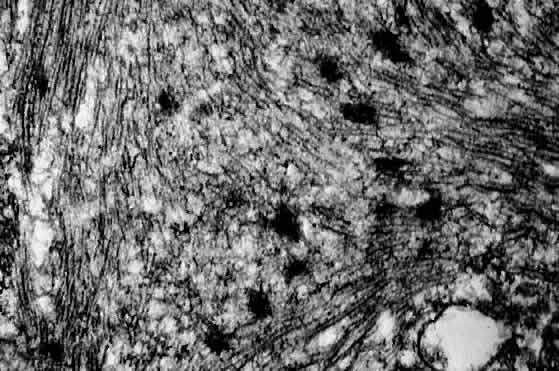

RMS was first reported in 1854 by Weber,50 but the conventional classification was developed by Horn and Enterline in 1958.51 The classification of Horn and Enterline describes four histologic variants of RMS: embryonal, botryoid, alveolar, and pleomorphic. Cross-striations (i.e., striated muscle differentiation) are seen only in approximately 60% of the lesions. Wilder's stain for reticulin may demonstrate the cross-striations more effectively.49 Electron microscopy49,52,53 (Fig. 2) and immunohistochemical staining for myosin, myoglobin, and desmin may also assist in the diagnosis of RMS subtypes.47,49 In addition, recent progress in molecular genetics may allow RMS to be diagnosed with the use of reverse transcriptase polymerase chain reaction and other modern techniques.24,25,47,54

Fig. 2. Electron micrograph of rhabdomyosarcoma demonstrating Z-bands within the cytoplasm of tumor cells. (Courtesy of R. Jean Campbell, MB, ChB, Mayo Clinic, Rochester, Minnesota.)